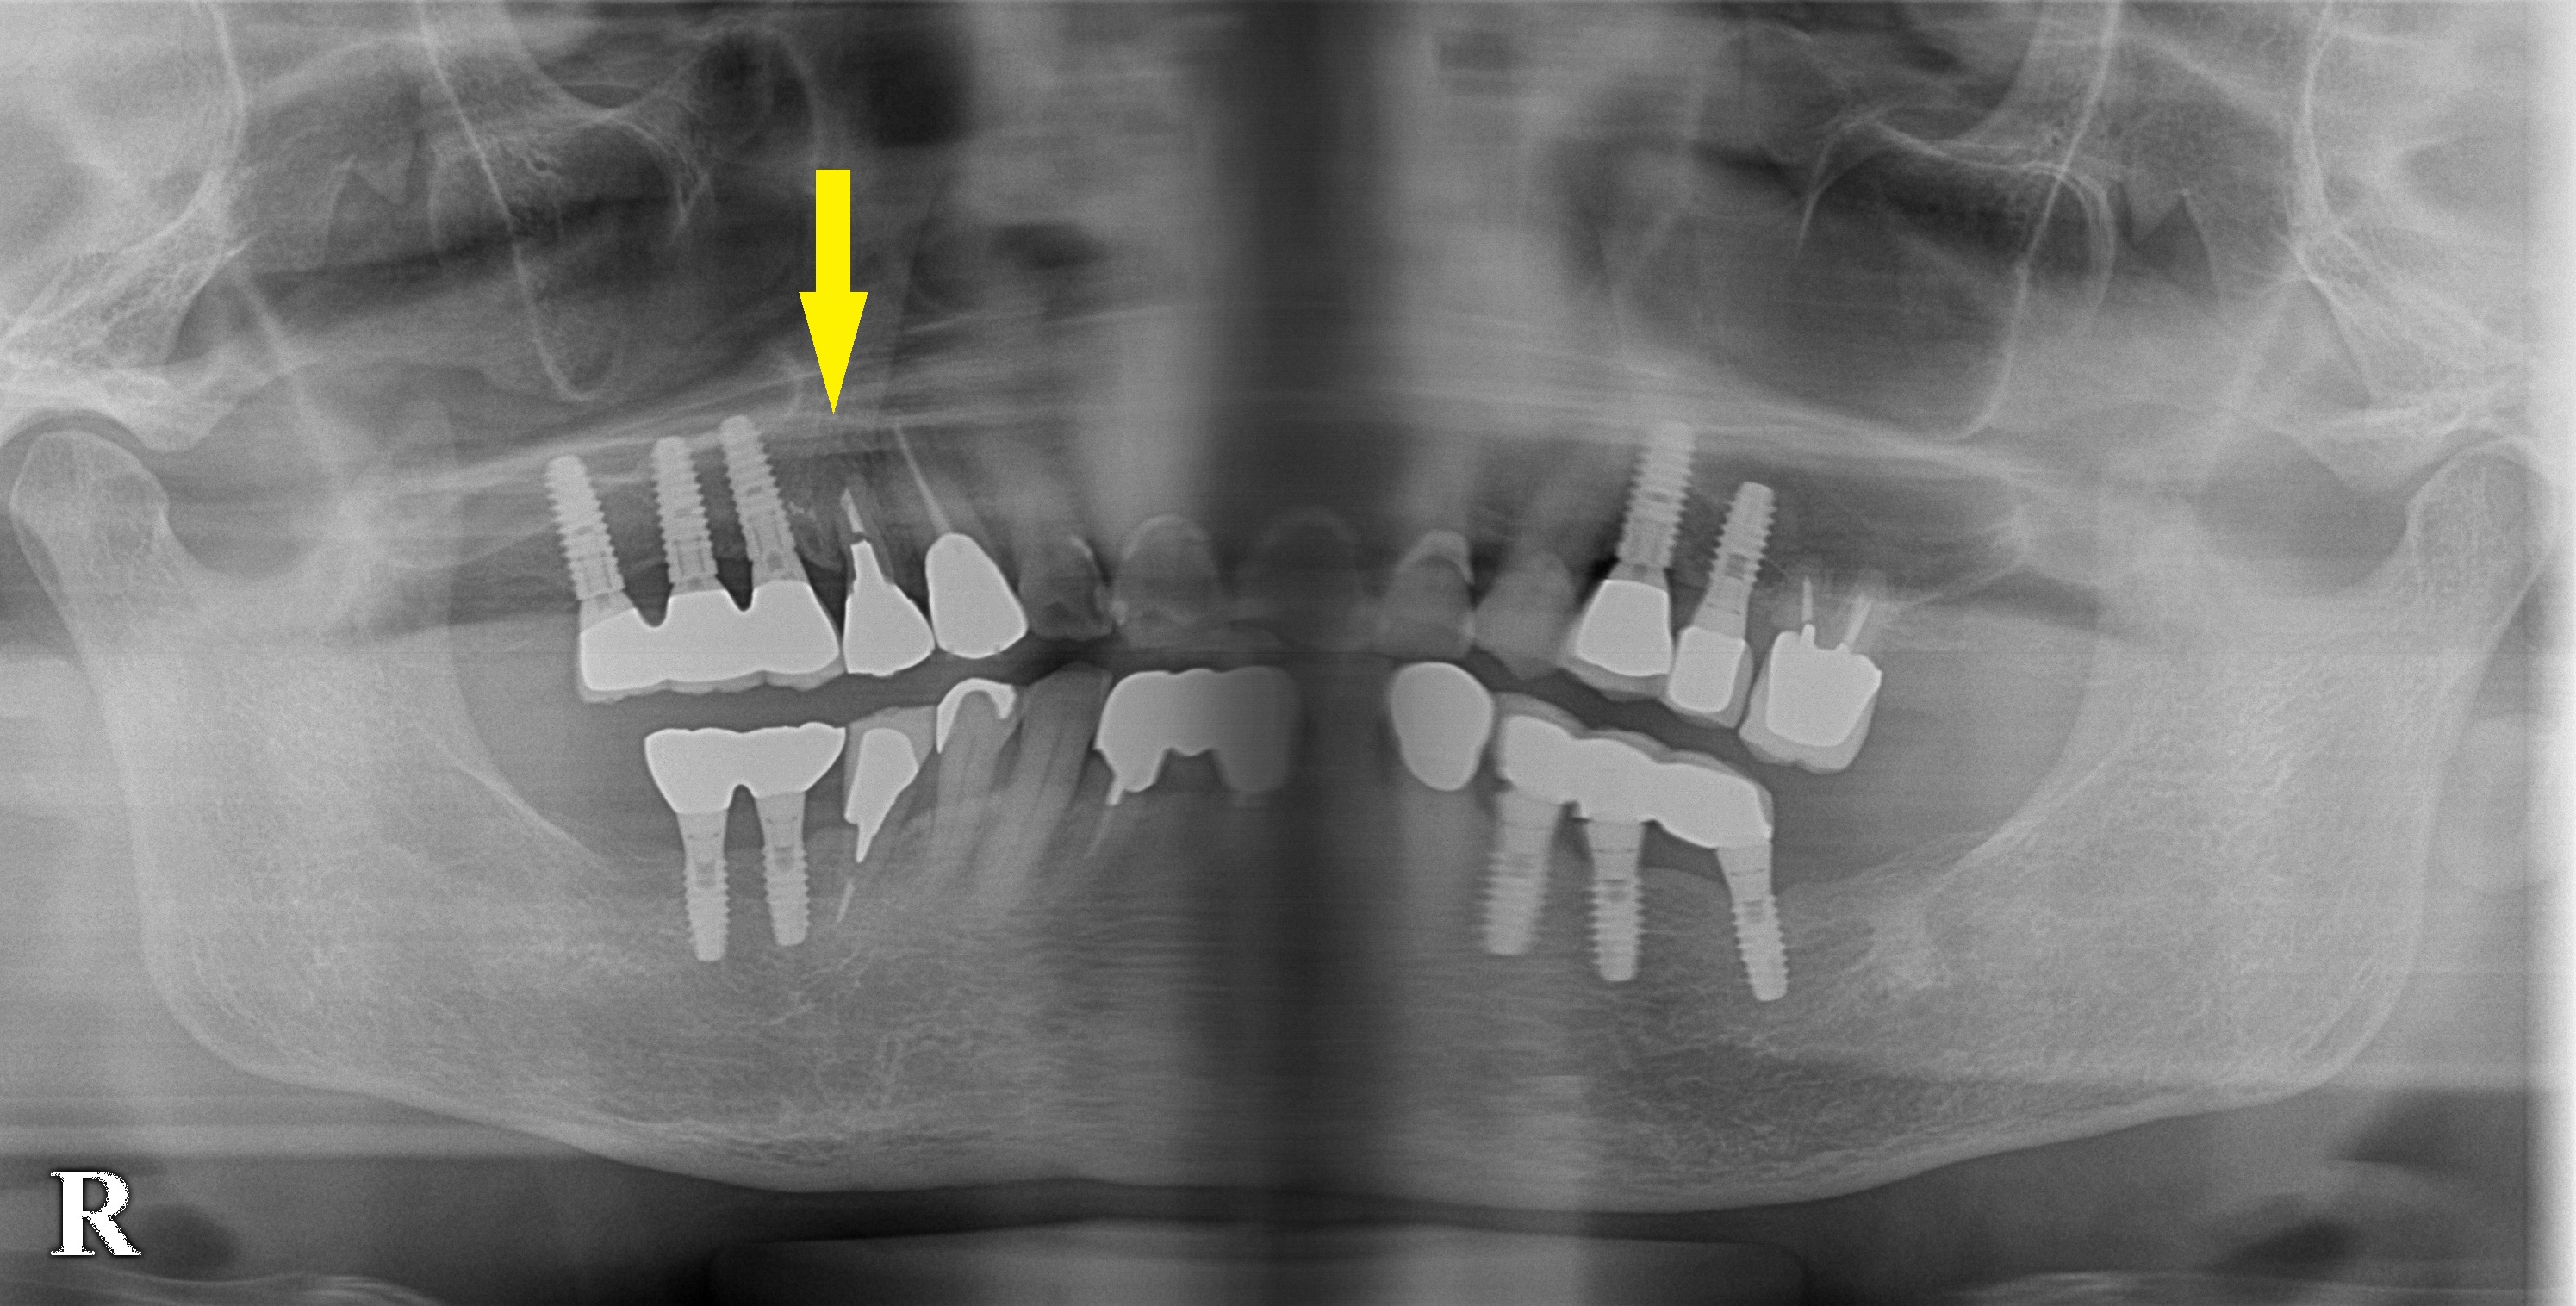

下段、右の写真が埋入後のCTです。

適切な方向と位置にインプラントが埋入され、黄色矢印部分に填入された骨補填材が認められます。